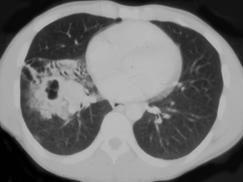

男,42岁,高热,寒战,咳嗽,胸痛1周左右,CT检查如图,选择最可能的诊断 ( )A、肺脓肿B、肺转移瘤C、肺癌D、肺囊肿E、肺结核

问题 男,42岁,高热,寒战,咳嗽,胸痛1周左右,CT检查如图,选择最可能的诊断 ( )

选项 A、肺脓肿 B、肺转移瘤 C、肺癌 D、肺囊肿 E、肺结核

答案 A